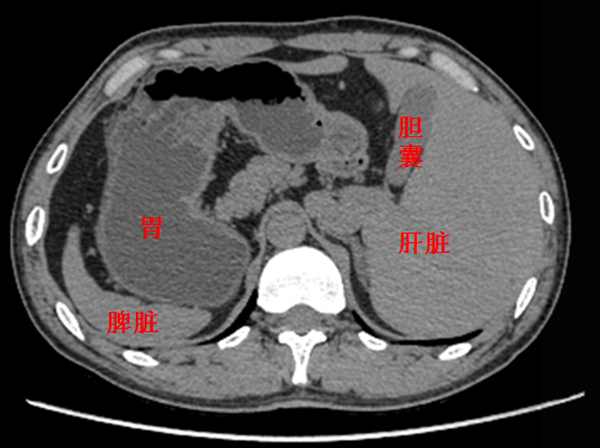

可意外的是,术前检查发现,刘先生竟然是罕见的“镜面人”。据夏强教授介绍,所谓“镜面人”,又称“镜子人”或“镜像人”,即心脏、肝脏、脾脏、胃等器官的位置与正常人相反,“比如正常人的心脏、脾脏在左边,镜面人则在右边,而正常人的肝、胆、阑尾长在右边,镜面人则在左边。就如同正常脏器的镜中像,发生率大约为万分之一。